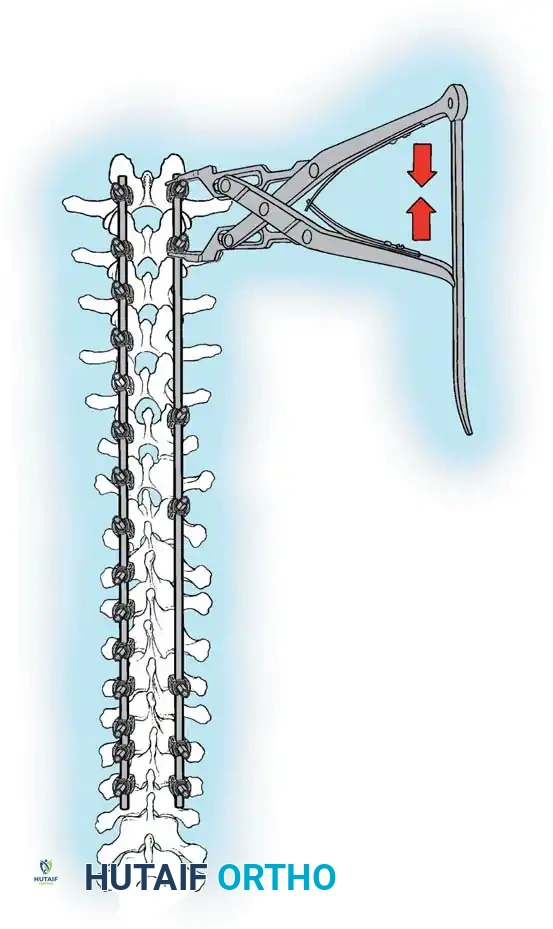

The Moe Technique (Lumbar Spine)

In the lumbar spine, the facet joints are oriented in a more sagittal plane, necessitating a modified approach.

Fig. 38-27: The Moe technique adapted for lumbar facet fusion, addressing the sagittal orientation of the joints.

- Utilize a small osteotome or a needle-nose rongeur to resect the adjoining joint surfaces.

- This creates a distinct rectangular defect within the sagittally oriented joint space.

- Pack this defect forcefully with cancellous bone graft.

- Proceed to decorticate the entire exposed posterior elements (laminae and transverse processes) using Cobb gouges, always directing force away from the spinal canal.